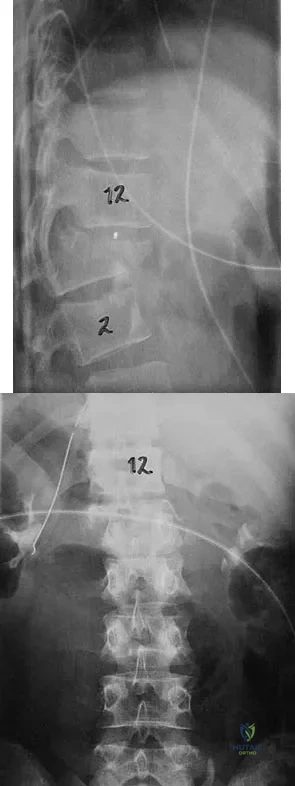

Figures 27a and 27b show the radiographs of a 32-year-old woman who was involved in a high-speed motor vehicle accident. She is neurologically intact. After stabilization and assessment, treatment should consist of

Explanation